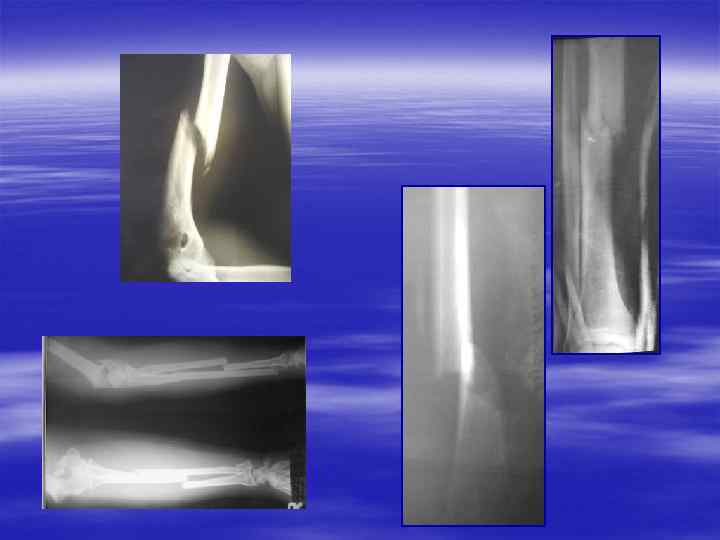

Без комментарий

Остеосинтез костей предплечья